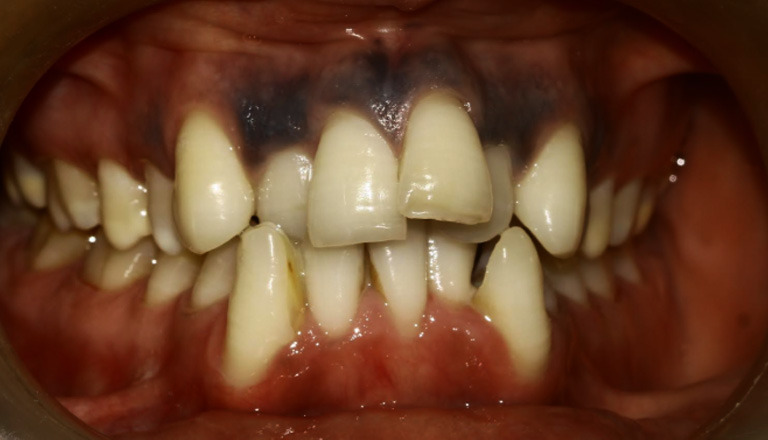

Intraoral Images: — (Before-treatment images)

The patient was diagnosed with Angle’s Class I malocclusion, along with crowded teeth and a crossbite. These conditions caused improper alignment of the teeth and an uneven bite.

Extraction of teeth 14, 24, 34, and 42 was performed as part of camouflage orthodontic treatment, followed by levelling and alignment of the teeth.